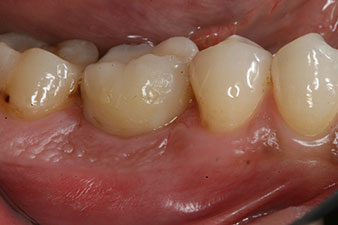

Figura 1: Situación clínica inicial después de la cicatrización del alvéolo de extracción de la pieza 36: la base del hueso es ancha y existe una cantidad suficiente de encía queratinizada.

En el paciente de 28 años con un historial de fumador severo, fue preciso extraer la pieza dental 36 como consecuencia de una recidiva de una periodontitis apical.

Como las piezas dentales adyacentes estaban en su mayoría intactas, el único tratamiento posible para los huecos existentes era un implante.